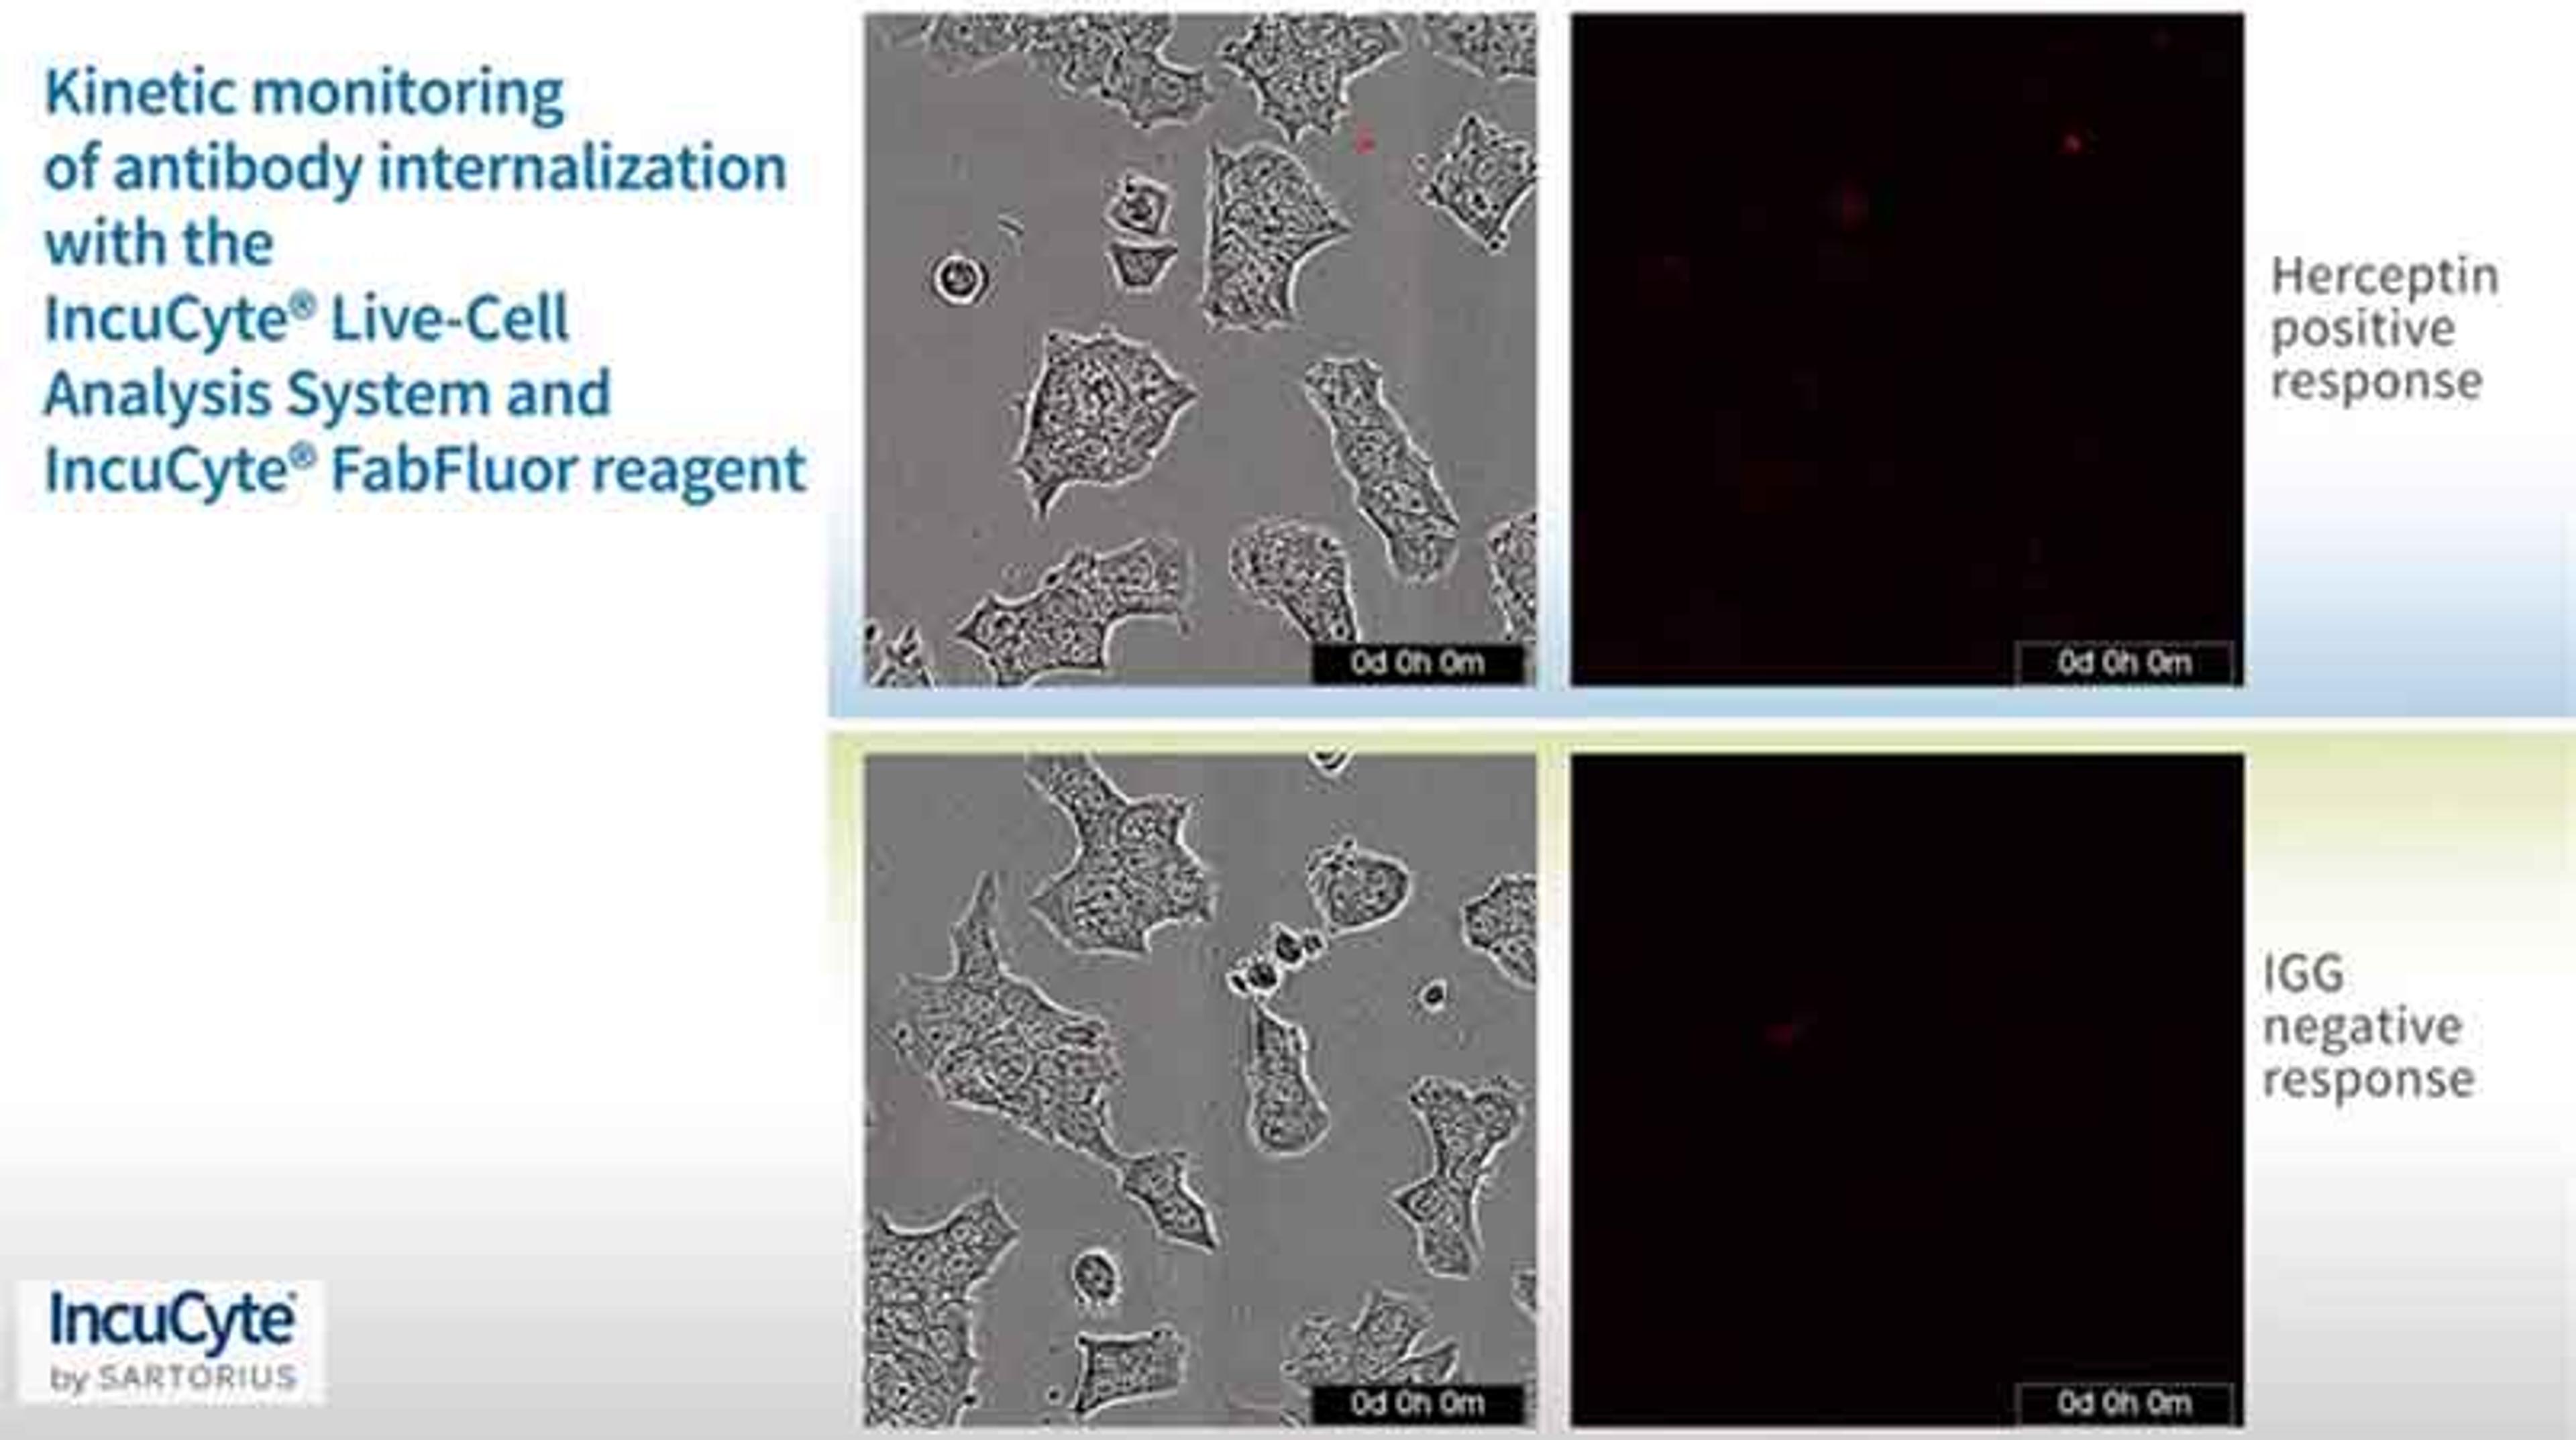

Analyze antibody or homing peptide-therapeutic agent internalization

The product is very effective for studying the internalization of complexes and also allows you to get highly reproducible results It is easy to use and has a convenient after-sale care. The cost of money is acceptable compared to the achievements obtained.

- Antibody Internalization